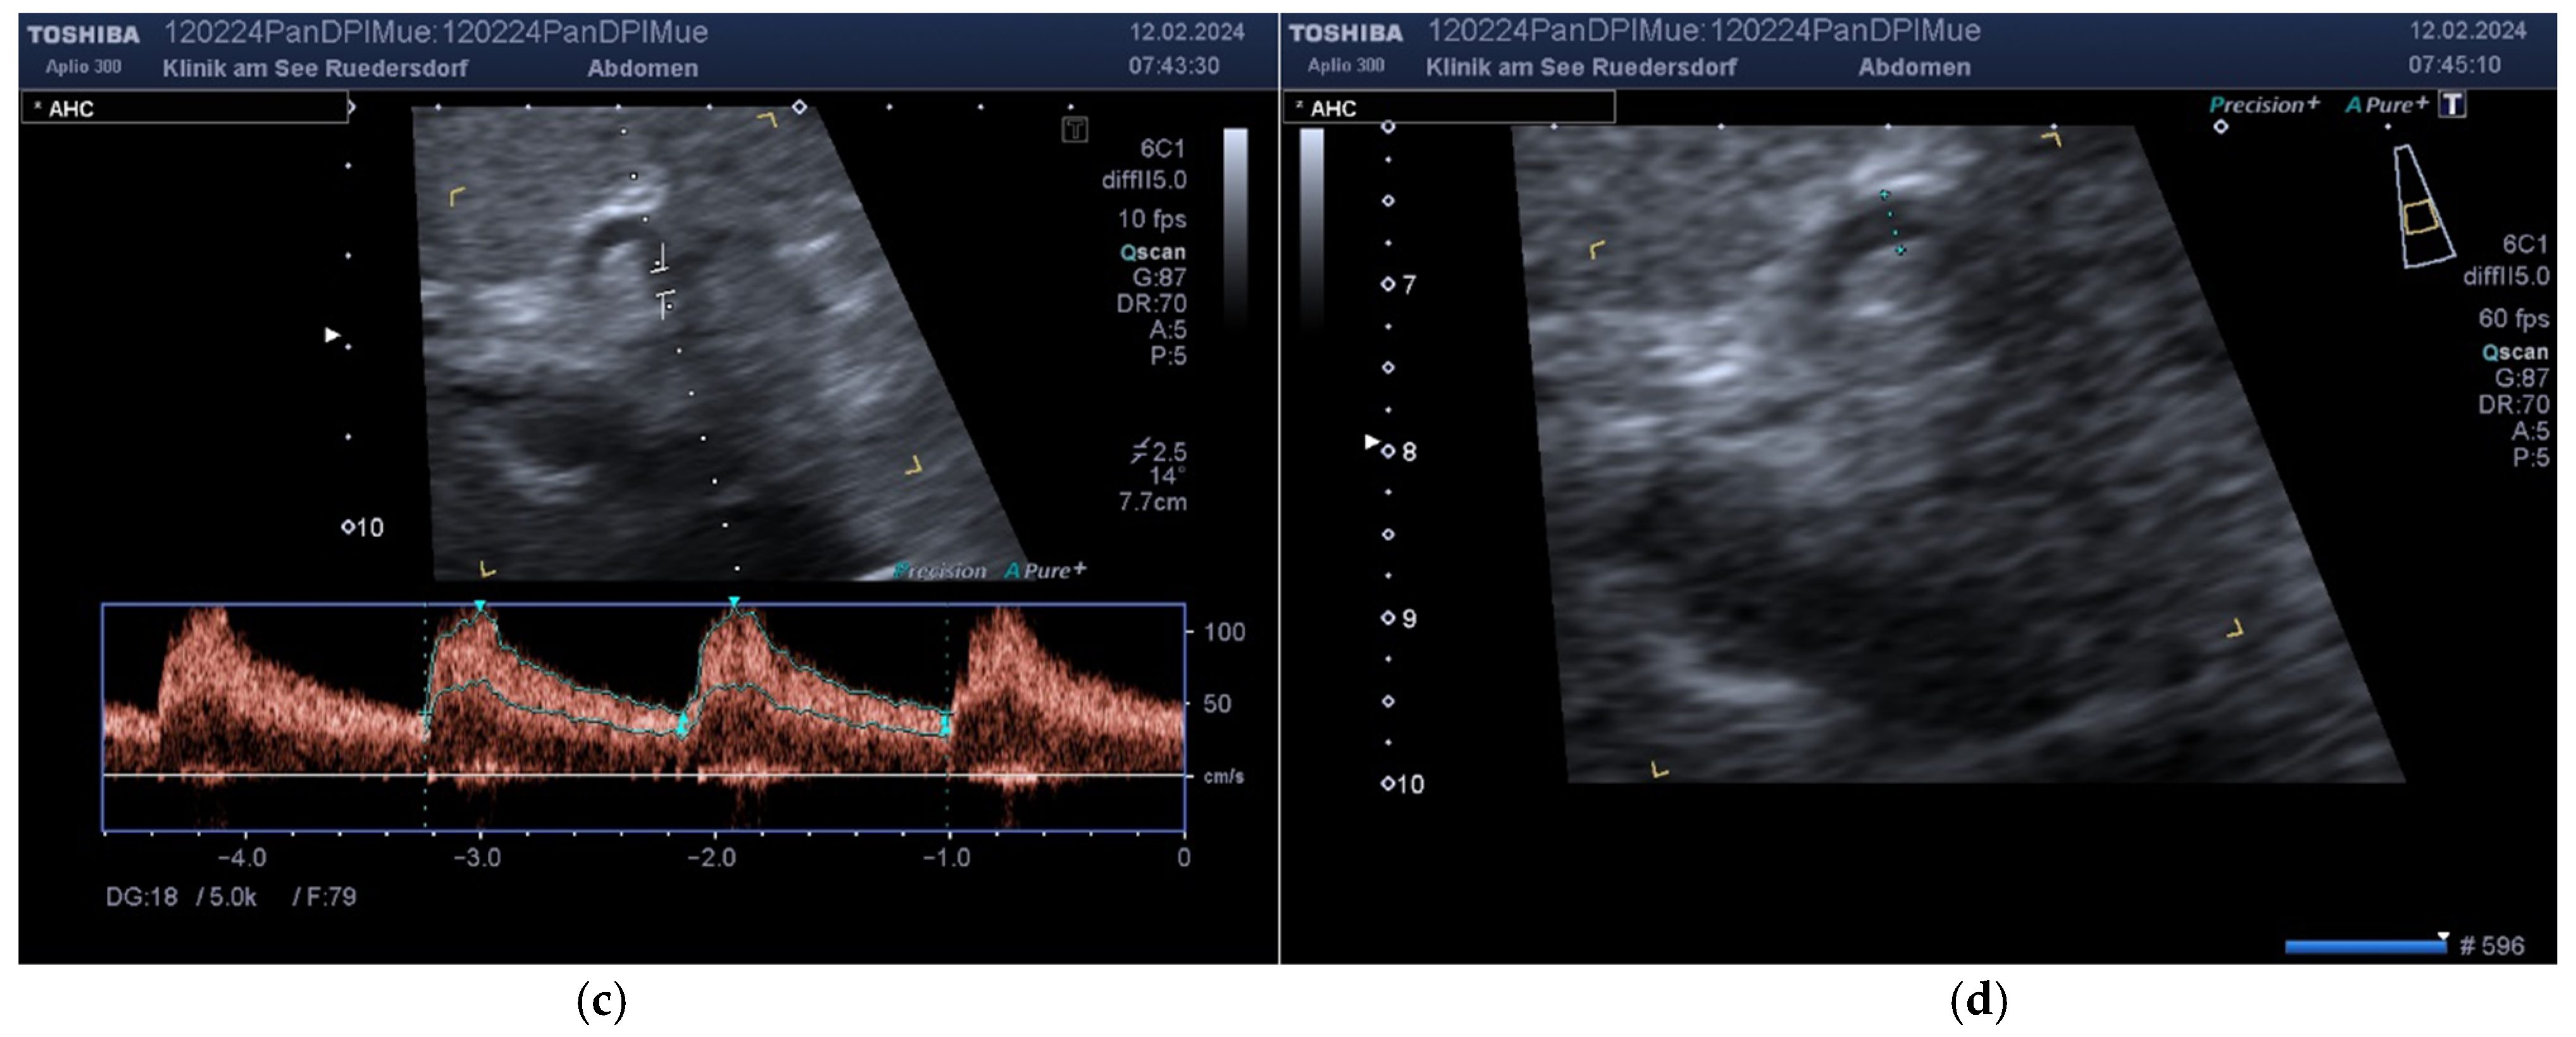

2.3.1. Determination of Vessel Diameter

2.3.2. Location of the Probe, Insonation Angle, and Doppler Window

2.4. Variables Acquired and Calculation of Blood Flows and DPI

- The vessel diameter (d, mm);

- The insonation angle (θ, degrees);

- The Doppler shift (V, cm/s);

- The resistive index for AHC and AHP (RI, non-dimensional).